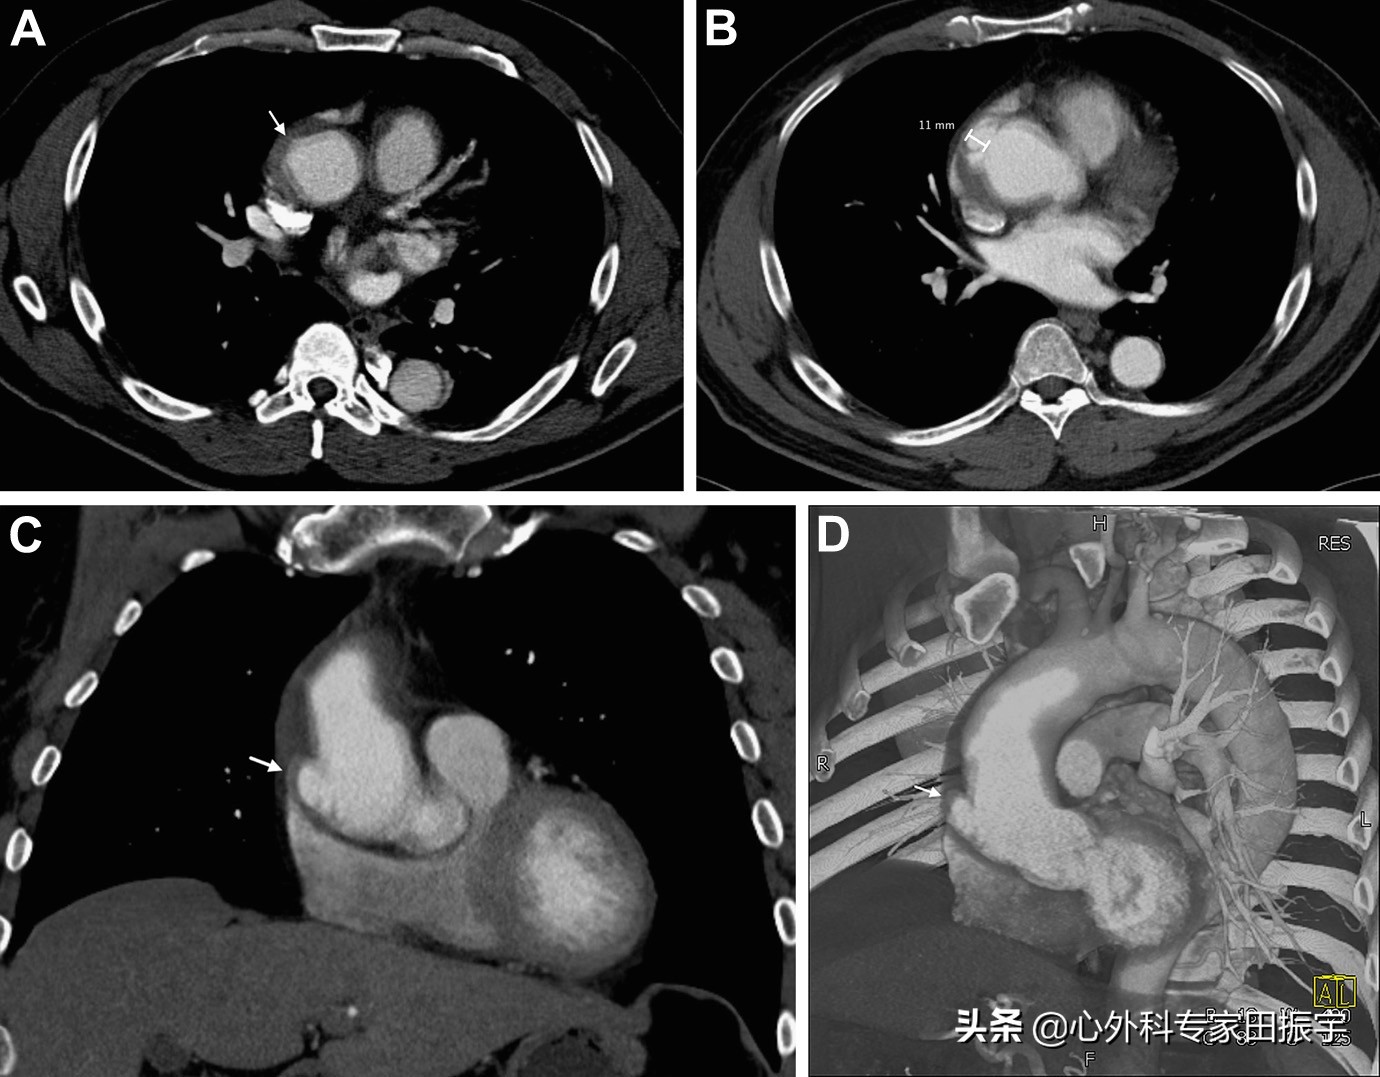

升主动脉溃疡

图2 一名64岁男子突然出现心前区疼痛。增强CT图像显示升主动脉前外侧壁A 型主动脉壁内血肿,微小的溃疡状投影(箭头)(A)。患者住院期间介入治疗直径6厘米肾动脉开口下的主动脉瘤。2个月后的随访增强CT图像显示,溃疡状投影(箭头)的动脉瘤扩大至11毫米深度,轴向(B),冠状方向(C)。通过三维体积重建图像 (D) 的倾斜方向部分显示溃疡状投影(箭头)与主动脉瓣的关系。这种大于10mm的溃疡状投影更有可能进展为其他并发症,如夹层、动脉瘤和破裂。